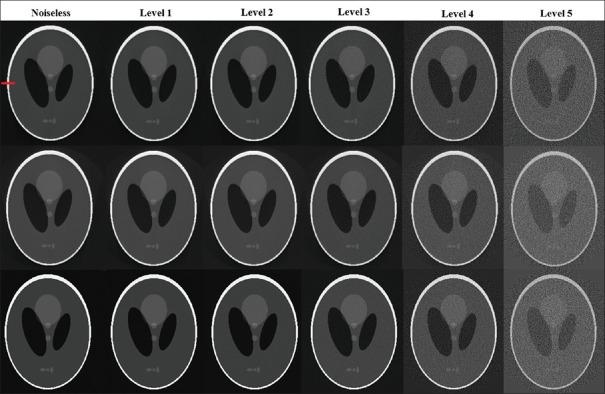

The contributing detectors for a given pixel and a given projection view, and the length of corresponding intersection lines with pixels, are calculated using our proposed algorithm. For the hybrid method, the respective narrow-angle fan beam was modeled by multiple equally spaced lines. The computed system matrix was evaluated in the context of reconstruction using the simultaneous algebraic reconstruction technique (SART) as well as maximum likelihood expectation maximization (MLEM).

RESULTS

The proposed LIM offers a considerable reduction in calculation times compared to the standard Siddon algorithm: 2.9 times faster. Differences in root mean square error and peak signal-to-noise ratio were not significant between the proposed LIM and the Siddon algorithm for both SART and MLEM reconstruction methods ( > 0.05). Meanwhile, the proposed hybrid method resulted in significantly improved image qualities relative to LIM and the Siddon algorithm ( < 0.05), though computations were 4.9 times more intensive than the proposed LIM.

CONCLUSION